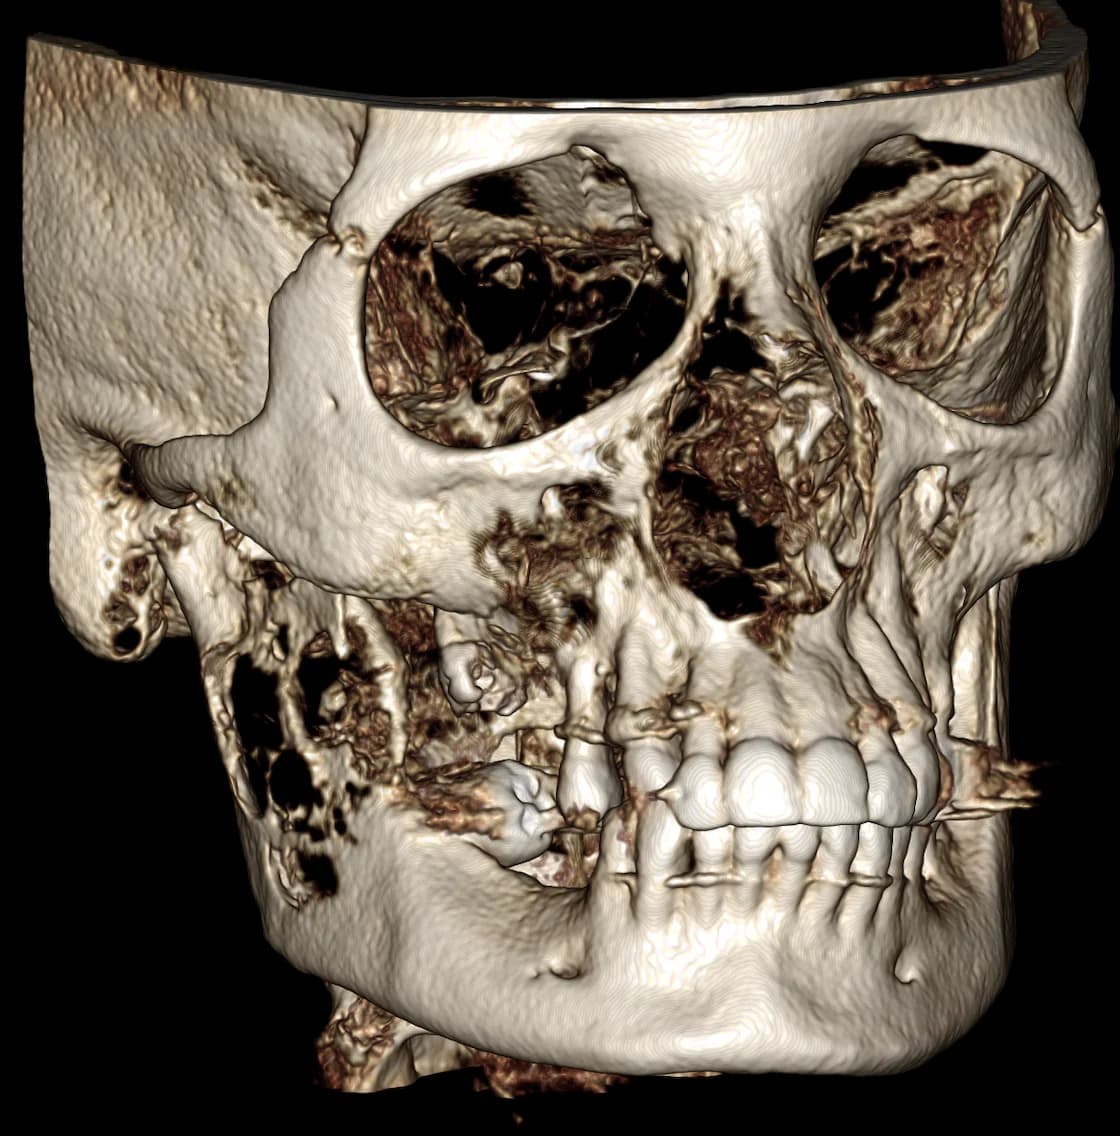

The oral and maxillofacial surgeon plays an essential role in treating oral pathologies, which can include a wide range of conditions affecting the tissues and structures of the mouth, jaw, and face. These pathologies can range from benign tumours to aggressive tumours and even malignant tumours. Early detection and management of certain conditions can have a significant impact on recovery and long-term prognosis. It may happen during a consultation with your dentist or family doctor that they notice an abnormality and are concerned about its nature. They will then send a consultation request for one of the surgeons on our team to examine you. After a thorough evaluation of the different structures of the face, oral cavity, jaws, and neck, and in some cases, taking x-rays, a biopsy may be necessary. A biopsy involves taking a tissue sample that is submitted for microscopic analysis by a pathologist. This can then help establish a treatment plan ranging from simple regular follow-ups to surgical treatment.